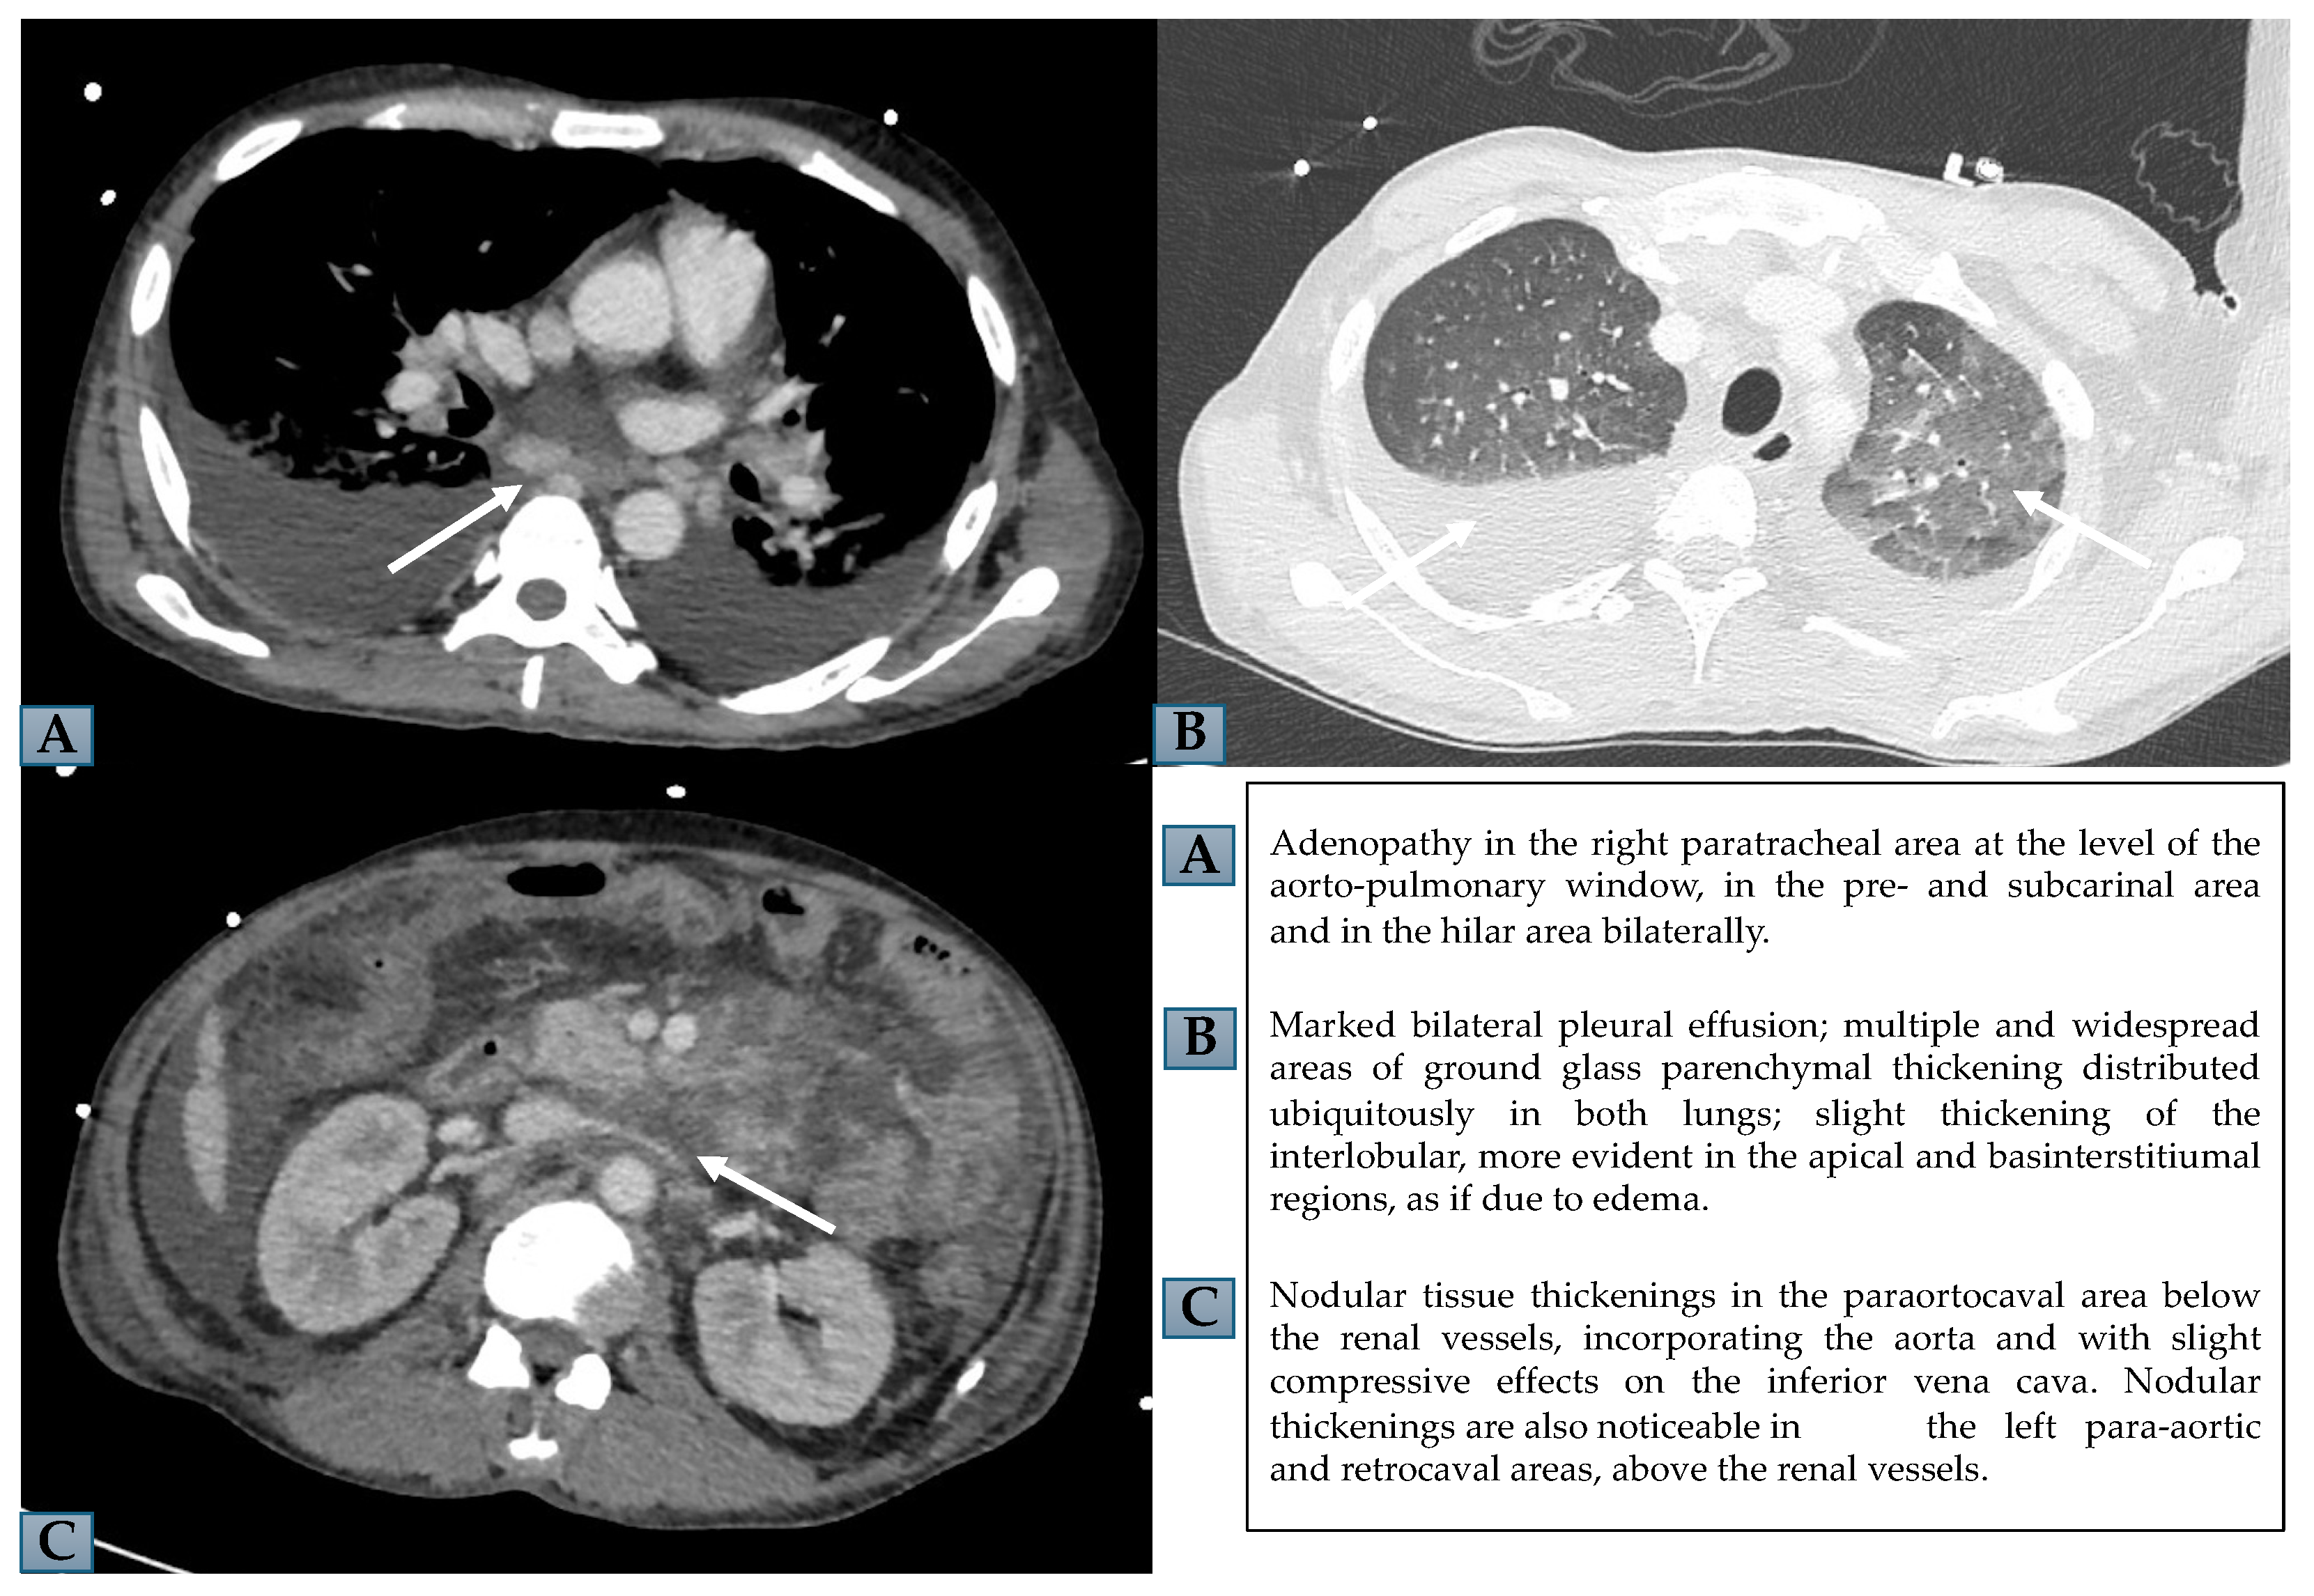

On the basis of these findings, HLH was suspected and several diagnostic tests were promptly performed, considering all possible differential diagnoses with diseases associated with hyperferritinemia. First, also in view of the recent trip to the home country, we ruled out the infectious cause of the fever; the blood culture and urine culture, the rapid malaria test and thick-drop smear, and QuantiFERON-TB Gold (QFT) for the detection of the cell-mediated immune response to specific Mycobacterium tuberculosis antigens, human immunodeficiency virus (HIV) antibody test, hepatitis B virus (HBV) markers, hepatitis C virus (HCV) antibodies, EBV antibodies, and cytomegalovirus (CMV) antibodies were all negative. On the chest X-ray, an effusion in the right hemithorax and diffuse parenchymal thickening suggestive of pneumonia were detected. Autoimmunity testing, including antinuclear antibodies (ANA), extractable nuclear antigens (ENA) and antineutrophil cytoplasmic antibodies (ANCA), was also negative. On the suspicion of lymphoproliferative disease, a total body computed tomography (CT) scan was performed. CT showed bilateral pleural effusion, pulmonary thickening, peritoneal effusion, and mesenteric lymphadenopathy with hilar abdominal and paratracheal adenopathy (Figure 1). Antibiotic therapy was then started with vancomycin, piperacillin/tazobactam and azithromycin and a glucocorticoid (GC) pulse of methylprednisolone, followed by dexamethasone.

Figure 1. Chest and abdomen CT. (A,B) show mediastinal adenopathy and bilateral pleural effusion with ground glass parenchymal thickening, in chest CT. (C) displays nodular thickenings in paraortocaval and retrocaval areas, in abdomen CT.